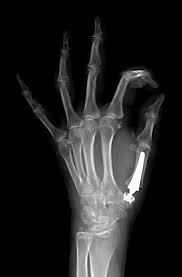

2) Cirugía de fusión: se realiza artrodiesis con placa o tornillos para fijar la articulación.

3)Prótesis de la articulación: se reemplaza el cartílago y hueso dañado por una protesis de materiales inertes, conservando el funcionamieno del pulgar.